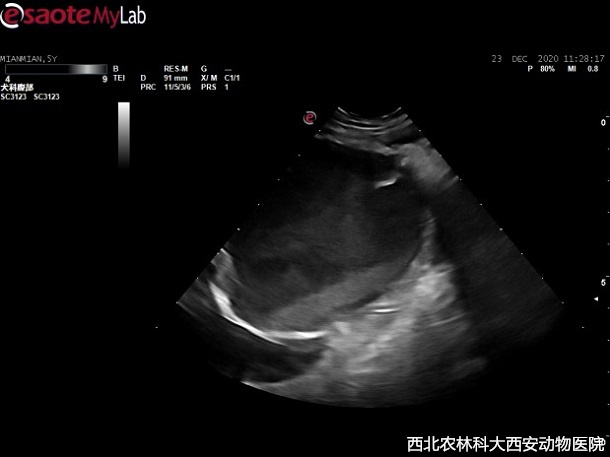

治療:經(jīng)與主人溝通,決定剖腹探查,分離粘連摘取占位,進(jìn)一步診斷并實施去勢術(shù)。術(shù)前對患犬的身體狀況進(jìn)行分級,ASA I級,給予麻前用藥,丙泊酚誘導(dǎo),吸入麻醉維持,實施剖腹探查占位摘除術(shù),術(shù)中抽放囊性結(jié)構(gòu),抽出液體為血水,經(jīng)查此占位與膀胱、前列腺和背側(cè)腹膜、腸系膜等均發(fā)生粘連,但無明顯組織來源見(圖2)。將摘除占位切開并放除內(nèi)部液體后,可見網(wǎng)狀結(jié)構(gòu)見(圖3)。手術(shù)期間至術(shù)后使用抗生素。占位送檢病理待查。

圖二 | 圖三 |